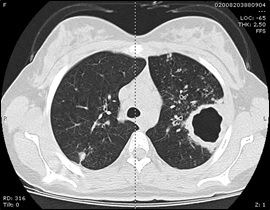

O estudo laboratorial revelou hemoleucograma normal e valores elevados de proteína C reactiva e velocidade de sedimentação. A radiografia do tórax evidenciou uma imagem hiperlucente arredondada associada a área hipotransparente no lobo pulmonar superior esquerdo (Figura 1). Foi efetuada tomografia computorizada pulmonar que confirmou lesão cavitada no lobo superior do pulmão esquerdo, medindo cerca de 50mm de maior eixo, associada a área de consolidação pulmonar (Figura 2), sendo a imagem compatível com infeção respiratória, nomeadamente, micobacteriose – tuberculose pulmonar (TP) e, posteriormente, confirmada por exame directo e cultural de expectoração.